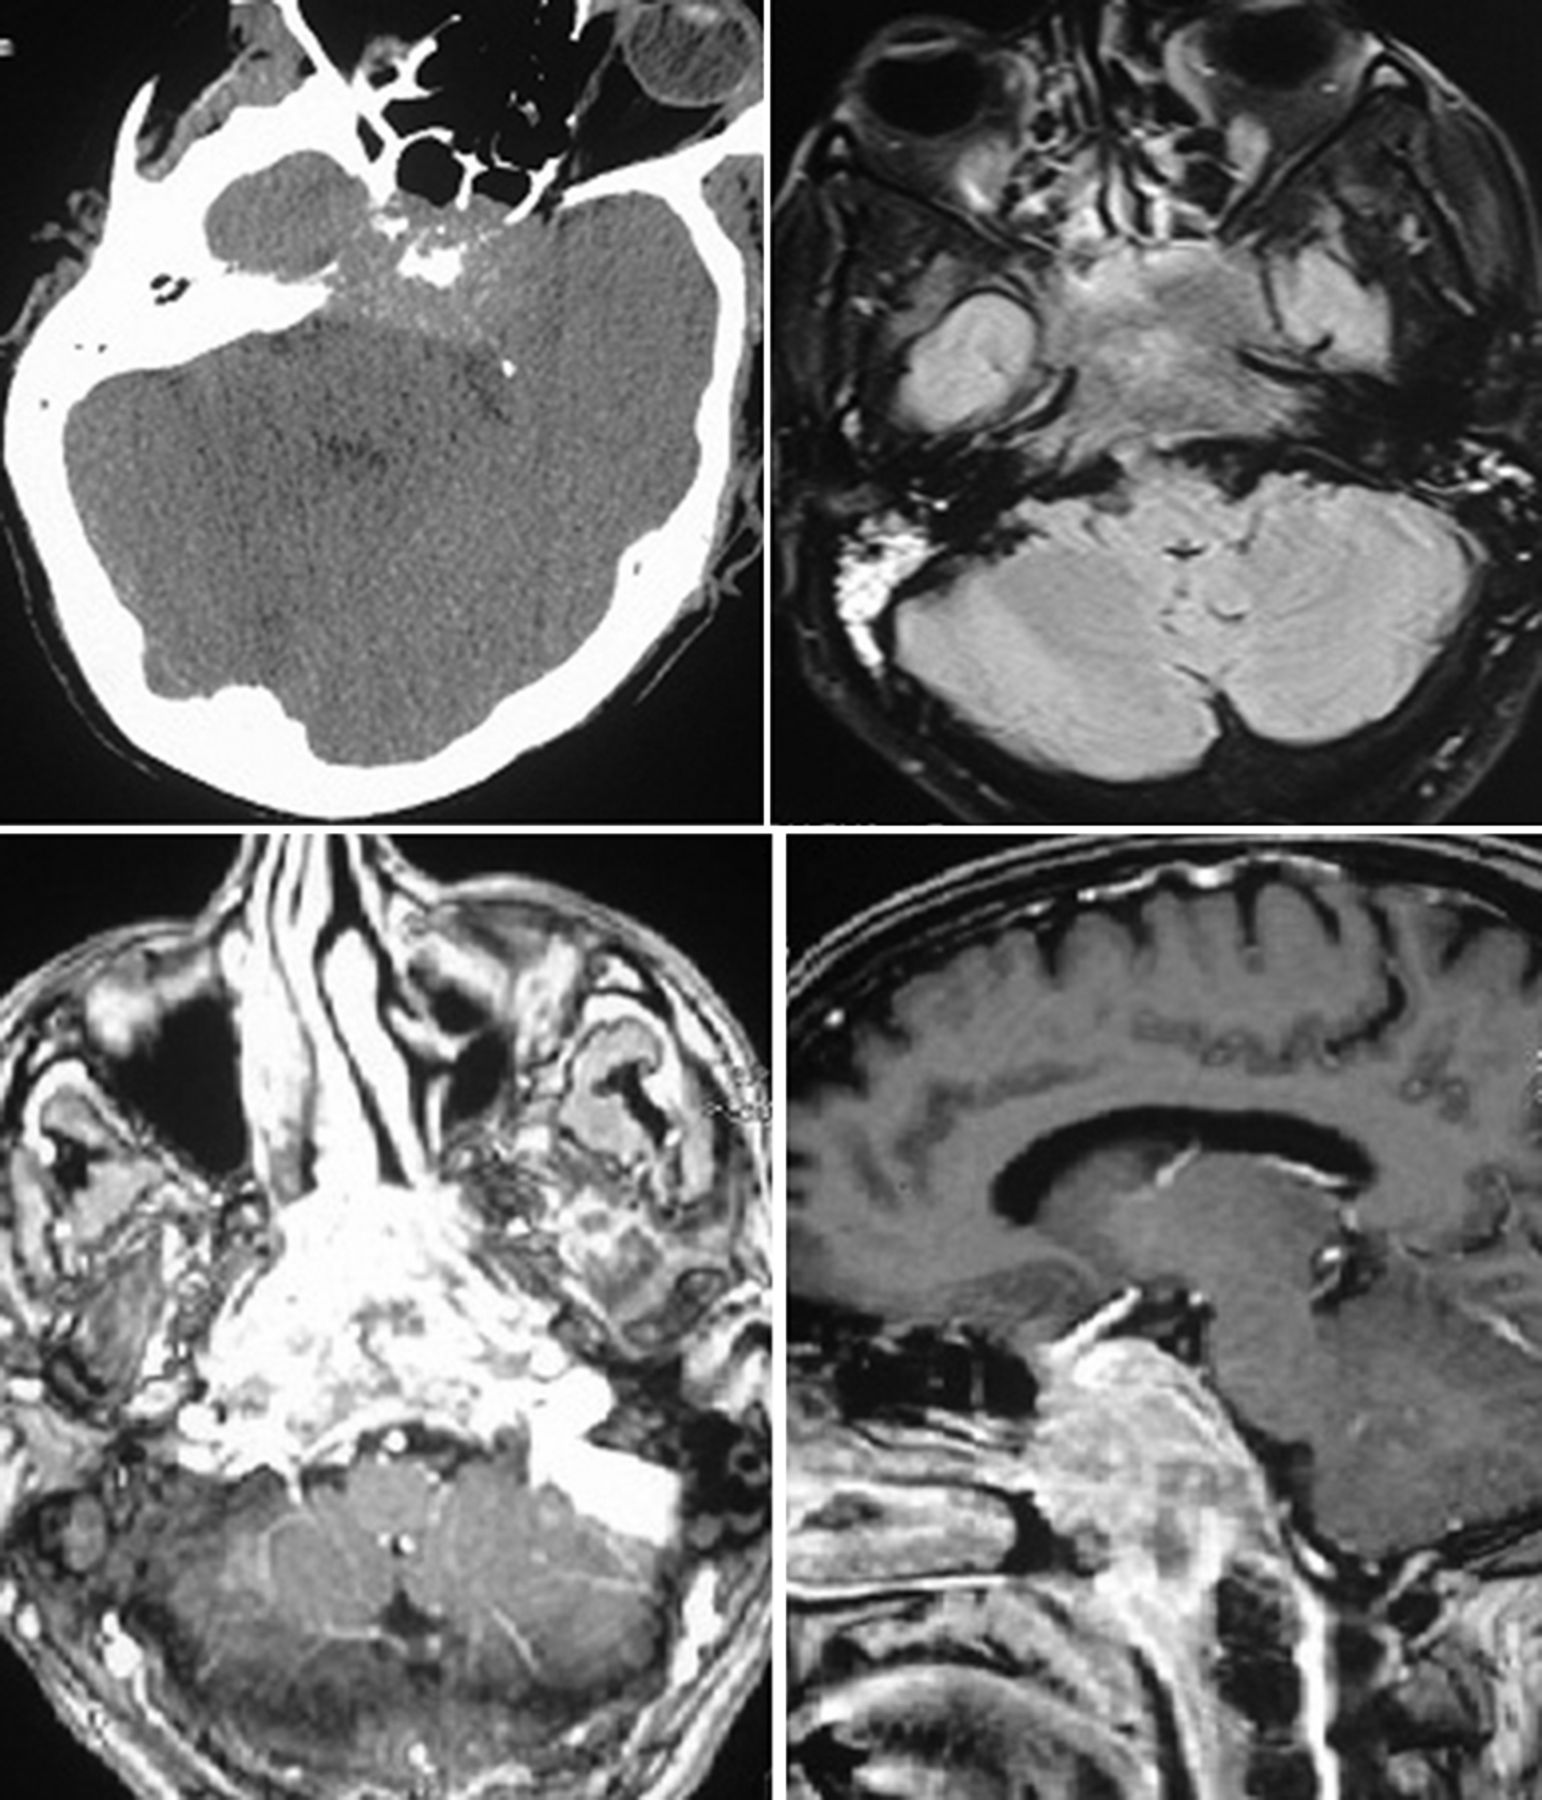

一个48岁的男子向我们医院急性发作,严重,持续holocranial头痛3个月的时间。他还指出双眼水平复视,左眼睑下垂,向内偏差的左眼开始的同时,头痛。症状逐渐恶化,在几周内他下垂的眼睑。他还抱怨逐渐进步与耳鸣听力损失,开始在左耳和右耳进展。没有其他系统性或神经系统症状。没有吸烟或吸毒或酗酒的历史。他的职业是一名保安。一般体格检查显示公司1×1厘米无痛颈部淋巴结。眼科检查发现两国第六,双边部分第三,第四个颅神经麻痹(图1)。眼底检查没有显示任何异常。双边传导性听力损失也在场。剩余的神经系统检查是正常的。他被诊断出患有双侧海绵窦综合征和双边顺序传导性耳聋。病原学的可能性被认为在这个阶段包括非传染性的肉芽肿性条件(如结节病和Tolosa-Hunt综合症)、传染性病因(真菌、结核或其他慢性感染),或恶性肿瘤(主要sellar质量parasellar扩展,extrasellar质量与双边扩展到parasellar空间,或转移)。他的血液,血液葡萄糖、肾和肝功能检测,血清血管紧张素转换酶的水平,和脑脊液检查结果在正常范围内。艾滋病毒血清学是负面的。他接受了41的头部CT扫描(图2),它显示一个不明确的温和hyperattenuating质量造成破坏的蝶骨包括鞍和斜坡。质量扩展到parasellar地区,蝶窦,prepontine地区双边。在核磁共振成像(图2),一个大鼻咽的质量被认为涉及后上的方面,以及楔形骨破坏的鞍和斜坡,保留基部的动脉。包裹内部质量颈动脉无腔的妥协。似乎与中央hypointensity isointense t1加权成像和在t2加权像上hyperintense异构postcontrast增强。

头部CT显示了一个不明确的温和hyperattenuating质量造成破坏的蝶骨包括鞍和斜坡。T2 fluid-attenuated反转恢复图像显示质量涉及蝶骨鞍和斜坡的破坏邻近结构进一步扩展。Postcontrast t1加权图像显示异构对比增强鼻咽癌质量与纵向扩展。

这个案例说明了诊断的困难人大在早期阶段由于各种原因,包括最初的非特异性症状和问题与考试相关的鼻后的空间。然而,仔细检查鼻咽往往揭示了病变。CT扫描与MRI补充目前肿瘤的精确定位,选择的调查和检测可能的肿瘤扩展,尤其是对颅底和深层面部空间。在目前的情况下,核磁共振还透露海绵窦的参与和扩展在鼻咽。CT扫描显示骨侵蚀的程度。